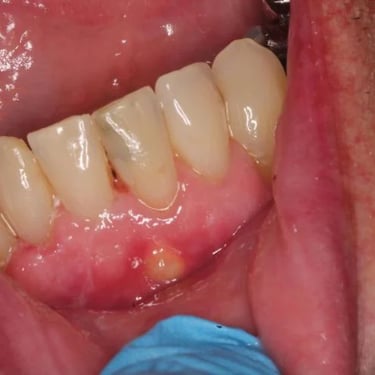

Pulpitis Crónica Hiperplásica

La pulpitis crónica hiperplásica es una inflamación de la pulpa con crecimiento excesivo de tejido pulpar a través de una caries abierta.

Los pacientes notan un tejido rojo que sobresale de la cavidad dental.

El tratamiento incluye la eliminación del tejido afectado y un tratamiento de conducto. Es crucial tratar la caries para evitar infecciones adicionales.